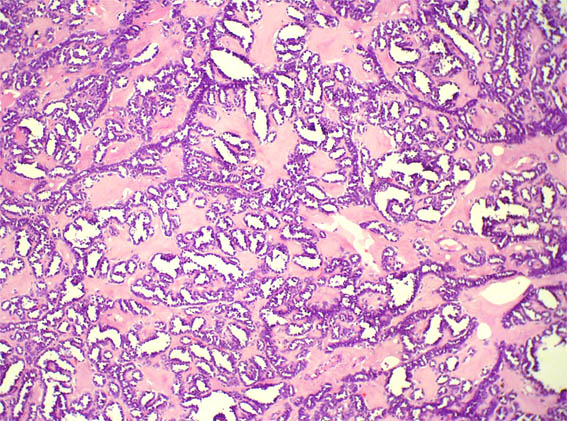

Figura 2.

H&E, X100.